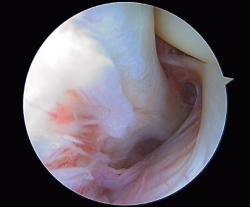

Tendón poplíteo en el hiato poplíteo

Popliteus tendon in the popliteal hiatus